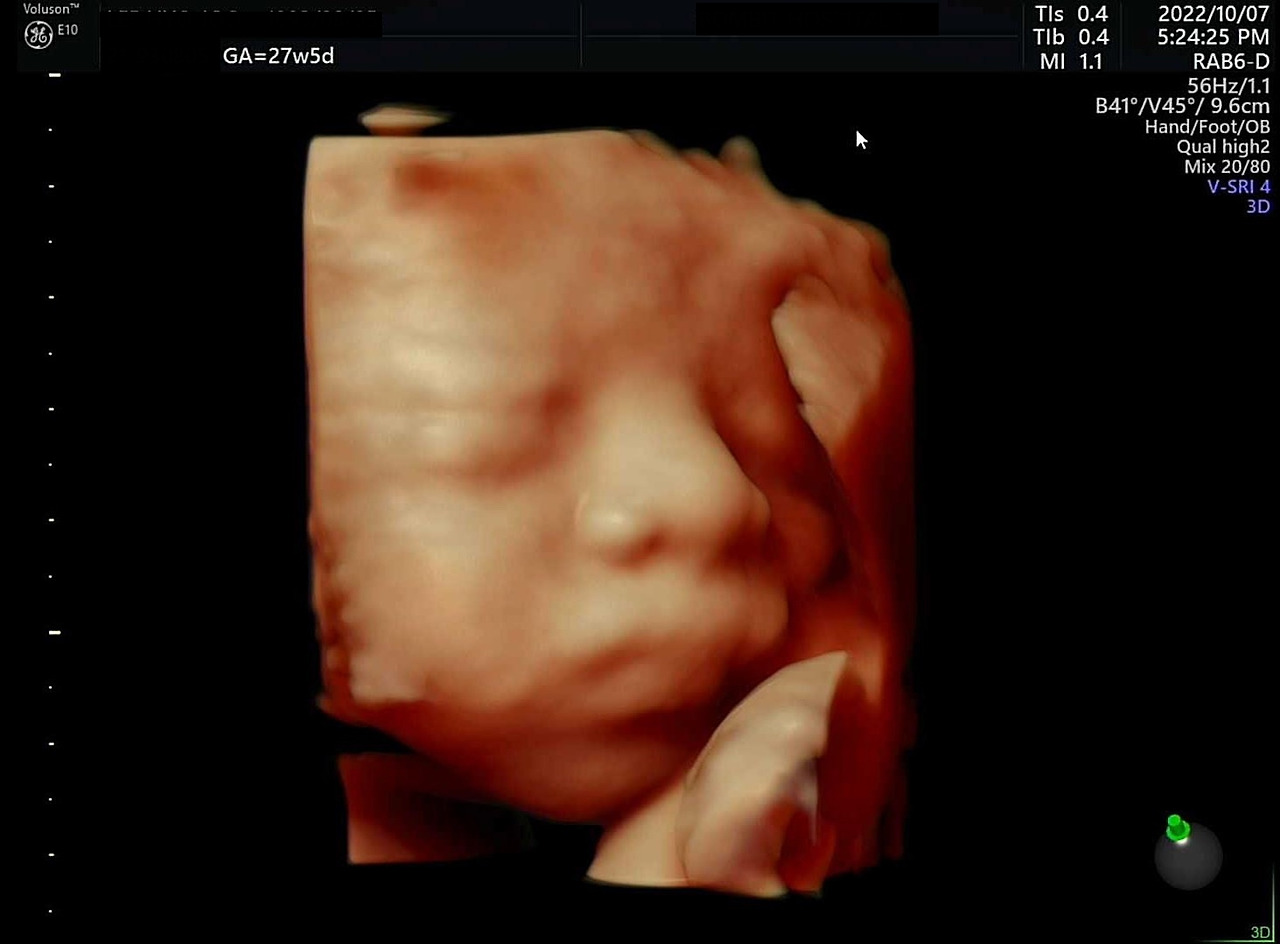

3차 시도 때는 아기가 팔을 내렸다. 그 대신 태반에 얼굴을 파묻고 있었는데, 내가 왼쪽으로 돌아누우니 얼굴과 태반 사이에 공간이 조금 생겨 사진을 찍을 수 있었다. 오똑한 코와 통통한 볼이 너무 예쁘다. 특히 우리가 초음파 사진을 보고 아빠를 닮았다고 확인했던 코 모양은 입체로 보아도 정말 아빠를 똑 닮았다. 작고 소중한 우리 아기, 엄마가 조금 귀찮게 해서 미안해! 그래도 얼굴 보여줘서 고마워♥

아빠를 똑 닮은 코, 특히 콧볼... 오른쪽은 양수를 먹고 있을 때 찍혀 입모양이 너무 귀엽다.